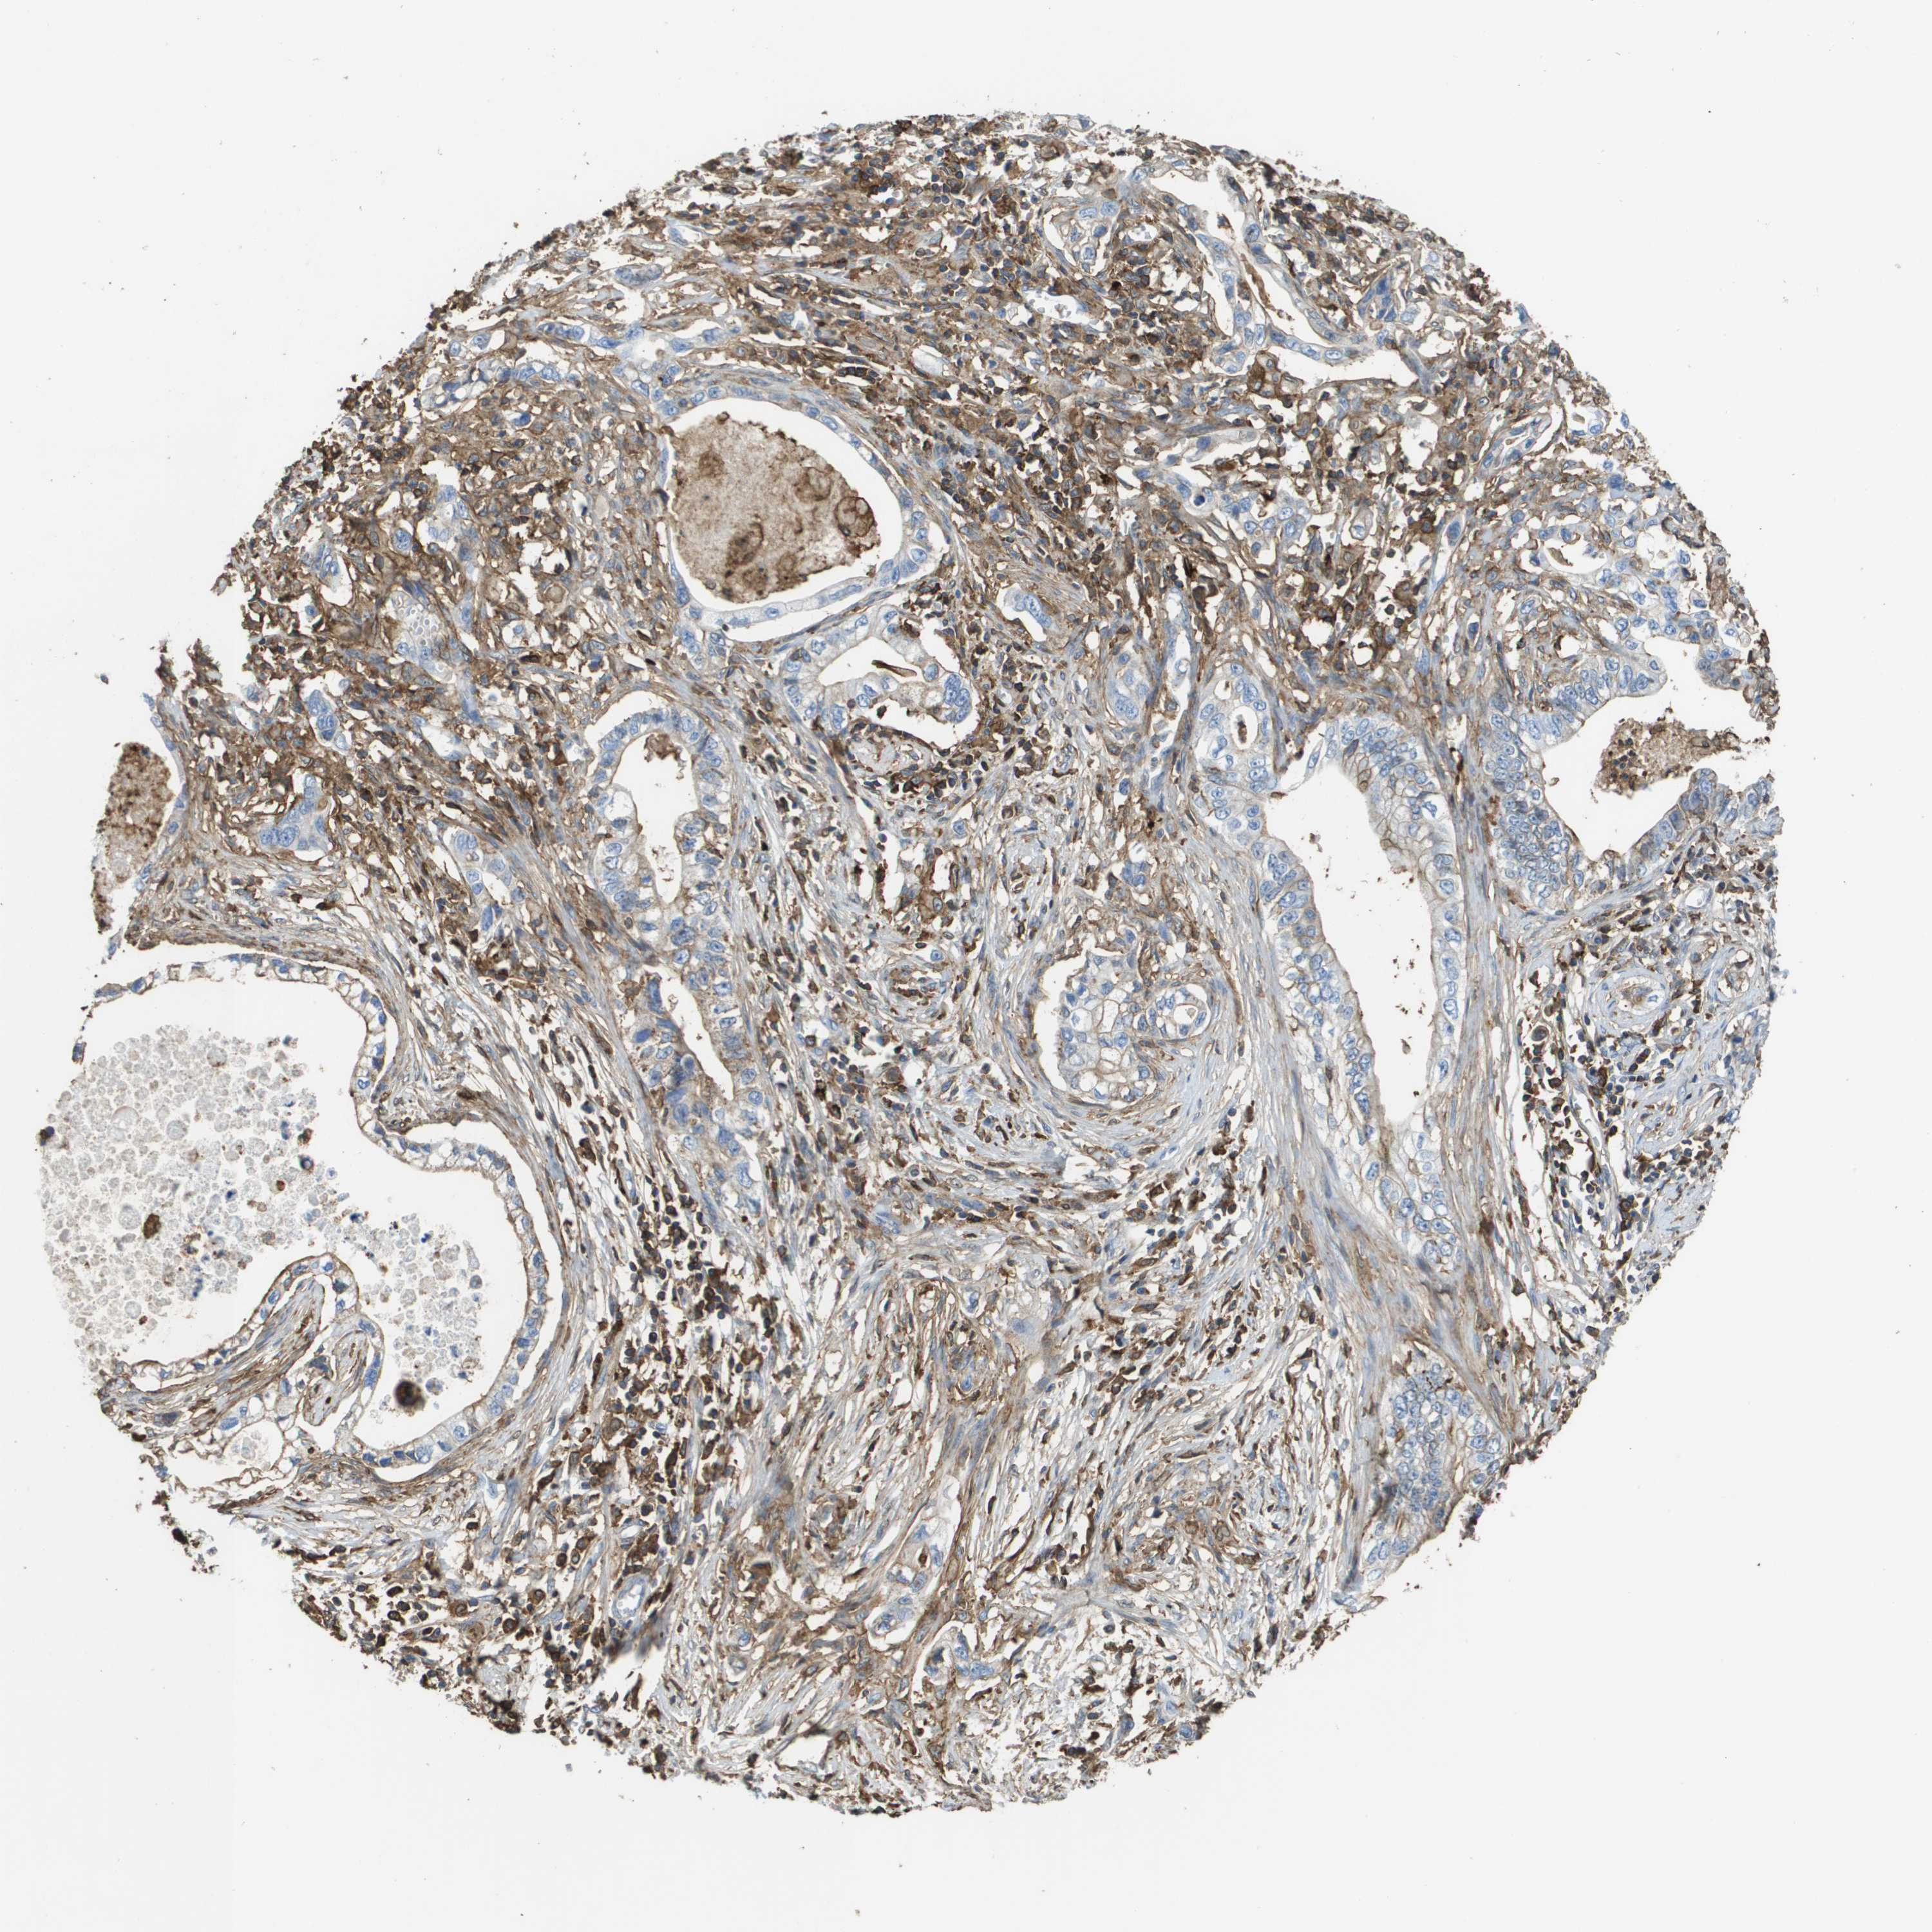

PANCREATIC CANCER - Protein expressioni

A mouse-over function shows sample information and annotation data. Click on an image to view it in a full screen mode. Samples can be filtered based on level of antibody staining by selecting one or several of the following categories: high, medium, low and not detected. The assay and annotation is described here.

Note that samples used for immunohistochemistry by the Human Protein Atlas do not correspond to samples in the TCGA dataset.

Antibody stainingi

Antibody staining in the annotated cell types in the current human tissue is reported as not detected, low, medium, or high, based on conventional immunohistochemistry profiling in selected tissues. This score is based on the combination of the staining intensity and fraction of stained cells.

Each image is clickable and will lead to virtual microscopy that enables deeper exploration of all samples and also displays staining intensity scores, fraction scores and subcellular localization as well as patient and tissue information for each sample.

Antibody HPA016450

Antibody HPA021079

Staining

High

Medium

Low

Not detected

Intensity

Strong

Moderate

Weak

Negative

Quantity

>75%

75%-25%

<25%

None

Location

Nuclear

Cytoplasmic/membranous

Cytoplasmic/membranous,nuclear

Adenocarcinoma, NOS